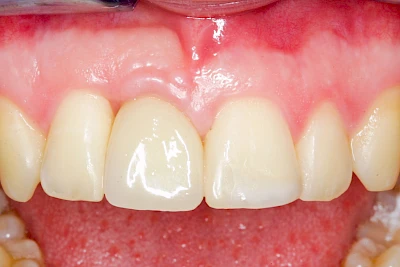

Implantate: Kronen & Brücken

Fehlen einzelne Zähne und die Nachbarzähne sind unbeschadet oder gut zahnärztlich versorgt, werden immer häufiger Implantate gewählt, um die Lücken zu schließen. Auch bei größeren oder verteilten Lücken, wenn keine herausnehmbare Prothese gewünscht ist, werden Implantate für Kronen- bzw. Brückenversorgungen gesetzt. In Einzelfällen entscheiden sich sogar zahnlose Patienten für eine festsitzende Versorgung auf Implantaten.

Varianten zur Verankerung von festsitzendem Zahnersatz auf Implantaten